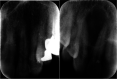

Figure 1

Pre-operative panoramic view, arrows show multifocal lesion. Periapical view of maxilla lesion